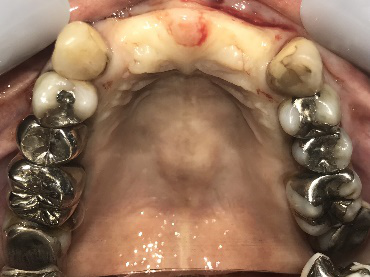

歯がグラグラするところ、むし歯のところ、しみるところ、被せ物がとれたところ、歯茎が腫れて血が出るところ、歯が抜けているところがある。すべて治したい。

残っている歯を抜歯し、上下インプラント治療をしました。

歯周病が進行している歯、むし歯が進行している歯がほとんどで、レントゲンを撮り、詳しく診てみると、ほとんどの歯を保存することができないことがわかりました。抜歯後は、入れ歯かインプラントの方法があります。治療開始前に患者さんに詳しく現状を説明し、治療法についてじっくり相談しました。自分の歯と同じような感覚で食事できるインプラント治療を選択されました。治療後、表情がとても明るくなり、口元がとても自然で10歳以上若返ったように感じました。「時間はかかりましたが、インプラントにして本当に良かったです!」と素晴らしい笑顔でお話ししてくださいました。